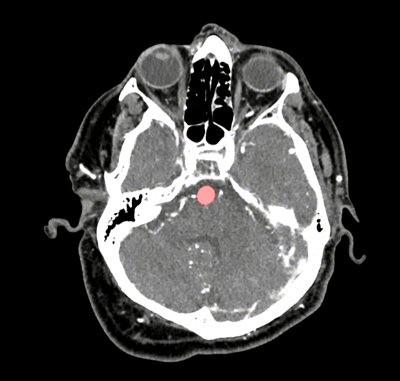

在脑部扫描中,HeadXNet使用透明的红色高光指示动脉瘤的位置。(图片来源:Allison Park)

对脑部扫描结果进行梳理、寻找动脉瘤意味着要浏览数百幅图像。动脉瘤有多种大小和形状,并以不同的角度向外膨胀——有些动脉瘤在一系列类似电影的图像中不过是一个光点。